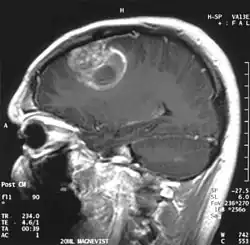

La tumeur peut prendre des apparences variées, en fonction de l'étendue de l'hémorragie ou de la nécrose, ou de son âge. Une scanographie (CT scan) montre généralement une masse non homogène avec un centre hypodense étendu en un anneau de taille variable entouré d'œdème. Il existe un effet de masse avec un déplacement possible du ventricule latéral et du troisième ventricule.

Le diagnostic d'un GBM suspecté lors d'un scanner ou une IRM repose sur une biopsie stéréotaxique ou une craniotomie, qui permet, par la même occasion, de retirer autant de tumeur que possible. Bien que la totalité de la tumeur ne puisse théoriquement pas être retirée, en raison de sa multicentricité et de son caractère diffus, une résection partielle peut tout de même prolonger légèrement l'espérance de survie.